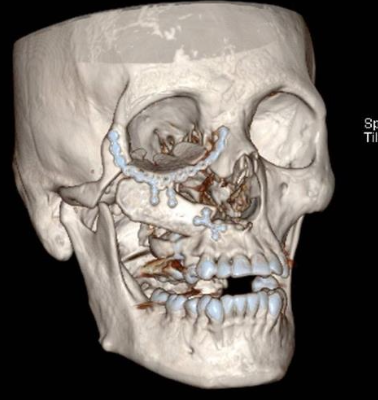

Imágenes y Cirugía

Diego Soto V, Cristian Marín O, Sebastián Morales Z